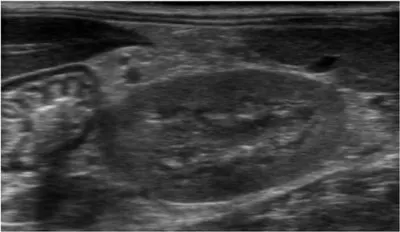

Thoracic radiographs (Figure 1) showed a diffuse bronchointerstitial pattern (reticulonodular). Abdominal radiographs demonstrated generalized hepatomegaly, gas-filled intestinal loops, and poor serosal detail. On abdominal ultrasound, the liver was hypoechoic and the cortices of both kidneys were hyperechoic (Figure 2). Functional ileus was present throughout the gastrointestinal tract.

Figure 2

The cortex of the left kidney is hyperechoic, making it isoechoic to the spleen (upper right) and hyperechoic to the liver (upper left).

There are numerous potential causes of acute renal failure to consider, but many can be eliminated from the differential list based on history and findings on the minimum database. Toxins, such as raisins, ethylene glycol, and ibuprofen, are often suspected. However, there are typically other significant findings, such as calcium oxalate monohydrate crystals and severely hyperechoic kidneys (ethylene glycol) or profound sedation (ibuprofen), in addition to renal failure. If pyelonephritis is suspected, sediment evaluation of the urine can identify the presence of pyuria and bacteriuria.